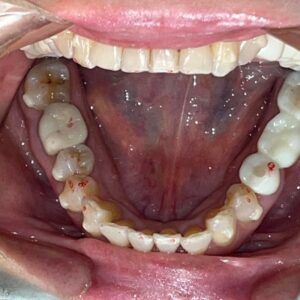

本日は、ジルコニアセラミック(歯科用人工ダイヤモンド)を使用した

メタルフリー治療の症例をご紹介いたします。

治療前は、メタルの詰め物が多数入っておりましたが、

患者様より詰め物を白くキレイにしたいとのことで治療を行いました。

Before After

メタルフリーになり、お口の印象がとても明るくなりました!

メタルフリー治療を行うと、審美的な改善が大きいですが

それだけではありません!

詰め物、被せ物にジルコニアセラミックを使用することで

経年的な摩耗や変色を最小限に抑える、

金属アレルギーのリスクがない、

歯質との適合性が高く、むし歯の再発リスクが低いなど、様々なメリットがあります。

前歯のレイヤリングジルコニアは特に色味や形態をぴったり合わせるため、

セラミストが写真撮影、デジタルトライインを行って作成します。

笑顔がさらに素敵になりましたね✨

患者様にも、とても喜んでいただけました😊